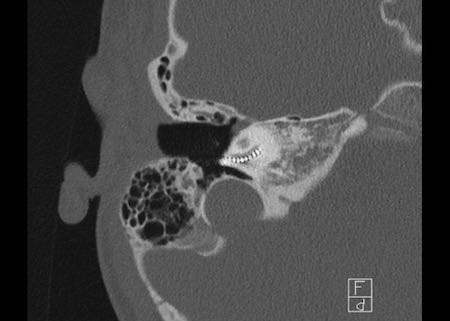

Bên trái là hình ảnh cholesteatoma lớn trong hòm nhĩ phải với phá hủy thành bên của hòm nhĩ.

Thân xương đe, nằm bên ngoài chỏm xương búa, cũng bị ăn mòn (mũi tên).